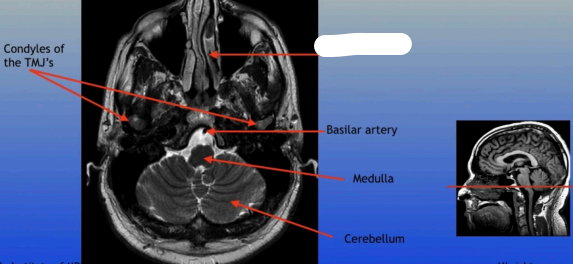

Condyles of the TMJ

Basilar Artery

Medulla

Cerebellum